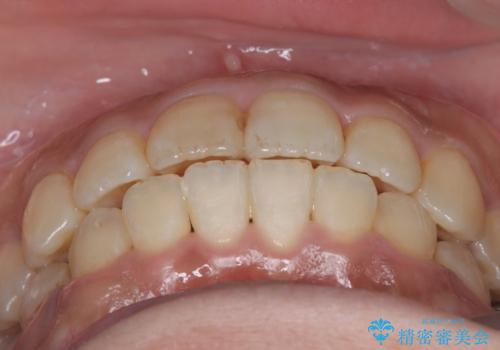

【ワイヤー矯正】前歯の凸凹を治したい

- 主訴:学生時代に矯正治療したが、後戻りしてしまった。上下前がのガタつきを治したい。

ワイヤー矯正(審美装置)非抜歯 治療期間:1年8か月